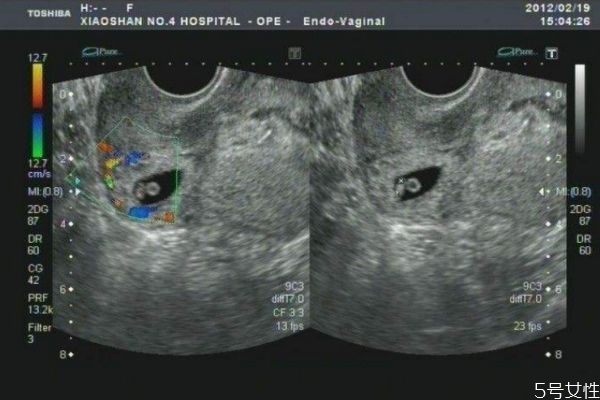

疤痕子宮就是說子宮已經(jīng)有疤痕,也就是說子宮已經(jīng)有過手術(shù)治療,比如子宮肌瘤的挖除,還有剖腹產(chǎn)的手術(shù),這些都是疤痕子宮。

越來越多的瘢痕子宮選擇再孕,這在一定程度上增加了妊娠并發(fā)癥和并發(fā)癥的風(fēng)險(xiǎn),前置胎盤上的子宮結(jié)合疤痕正在增加。過去四年中,危險(xiǎn)胎盤顯著增加,比2008年前增加了五倍。子宮切除術(shù)的比例增加了4倍。據(jù)報(bào)道,剖腹產(chǎn)后,前置胎盤的風(fēng)險(xiǎn)從0.38%增加到0.63%。當(dāng)?shù)谌螒言袝r(shí)存在前置胎盤時(shí),胎盤植入物的風(fēng)險(xiǎn)增加40%。子宮疤痕復(fù)發(fā),子宮破裂發(fā)生率約為1%。報(bào)告顯示,過去8年,婦女再次懷孕,有10例完全性子宮破裂,其中大部分為子宮肌瘤病史。只有一例涉及剖宮產(chǎn),有子宮肌瘤的拒絕史發(fā)生子宮破裂。破裂不是在先前的剖腹產(chǎn)疤痕處,而是在纖維瘤部位。因此瘢痕子宮的婦女雖然可以懷孕,但是面臨著重大的風(fēng)險(xiǎn)。